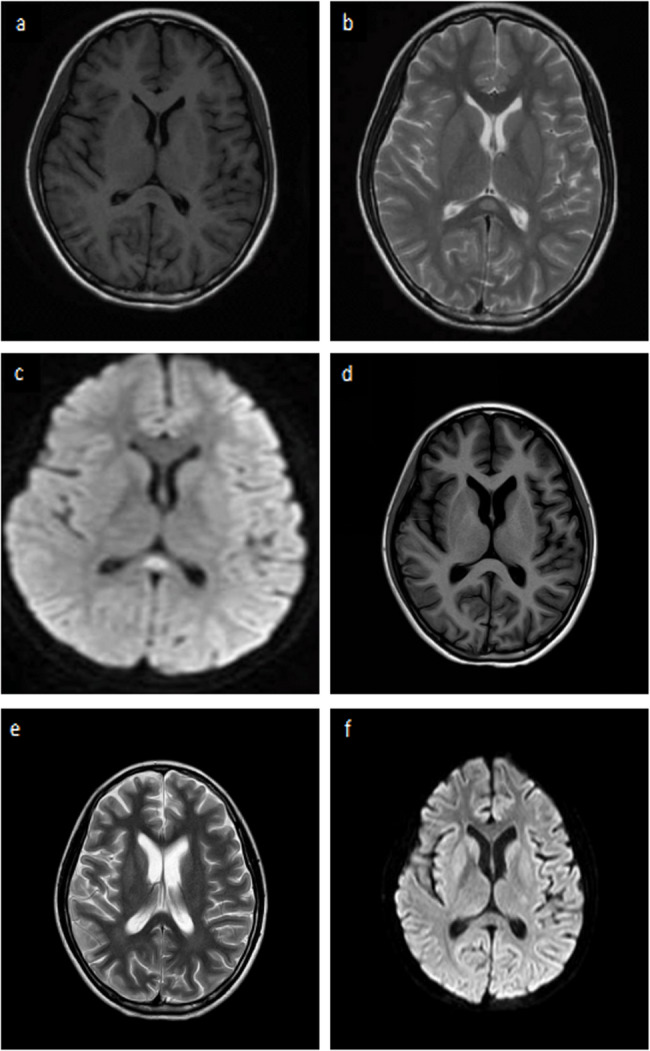

Mycoplasma pneumoniae infection and concurrent aquaporin-4-positive neuromyelitis optica spectrum disorder: a case report and literature review.